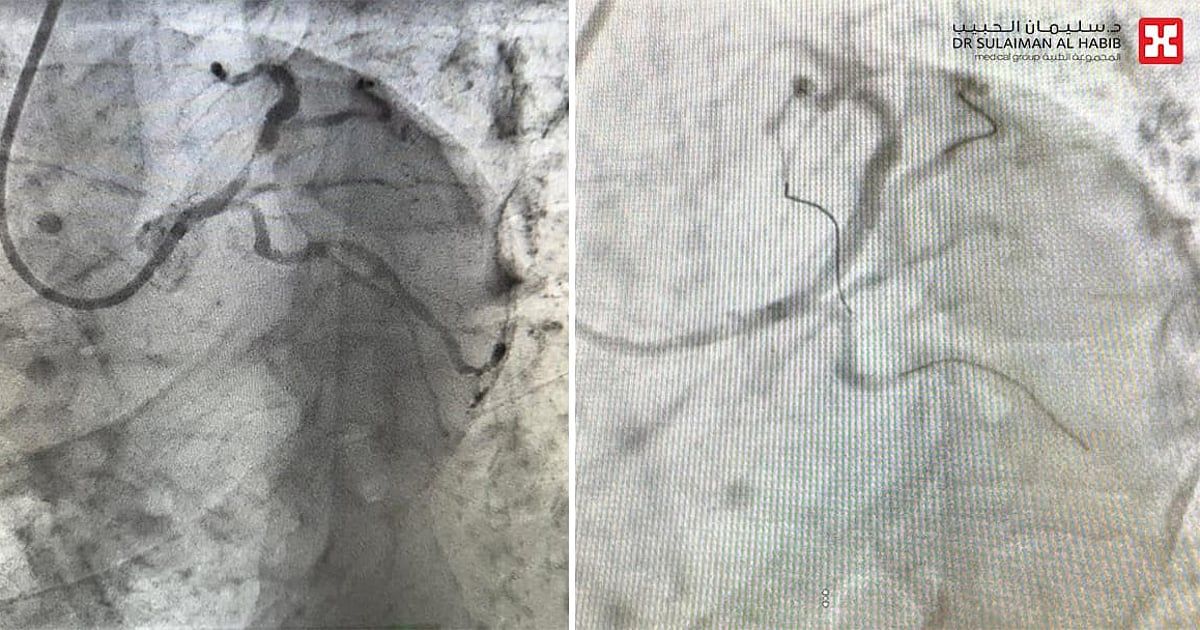

وقال د. الحربي أن المراجع أسعف إلى قسم الطوارئ، خلال وقت قصير من شعوره بالاختناق وعدم القدرة على التنفس، وكذلك آلام حادة بمنطقة الصدر، إضافة إلى أنه مصاب بأمراض مزمنة "ضغط الدم والسكري"، وأظهرت الفحوصات إصابته بجلطة حادة في الشريان التاجي الأيسر، وبعد تشخيص الحالة تم إدخاله مباشرة إلى غرفة الإنعاش القلبي ومنحه الأدوية المسيلة للدم، ثم نُقل لمختبر القسطرة القلبية، حيث تبين أن الانسداد حاد وبنسبة "99%"، وأجريت له عملية قسطرة طارئة، تم فيها، زراعة دعامة دوائية، وتأمين مرور الدم إلى القلب بشكل طبيعي، وكل ذلك تم في وقت وجيز من لحظة صوله إلى مركز الطوارئ، ثم نُقل إلى العناية المركزة للمراقبة، قبل أن يغادر إلى منزله بحالة صحية جيدة بعد أقل من "48" ساعة.